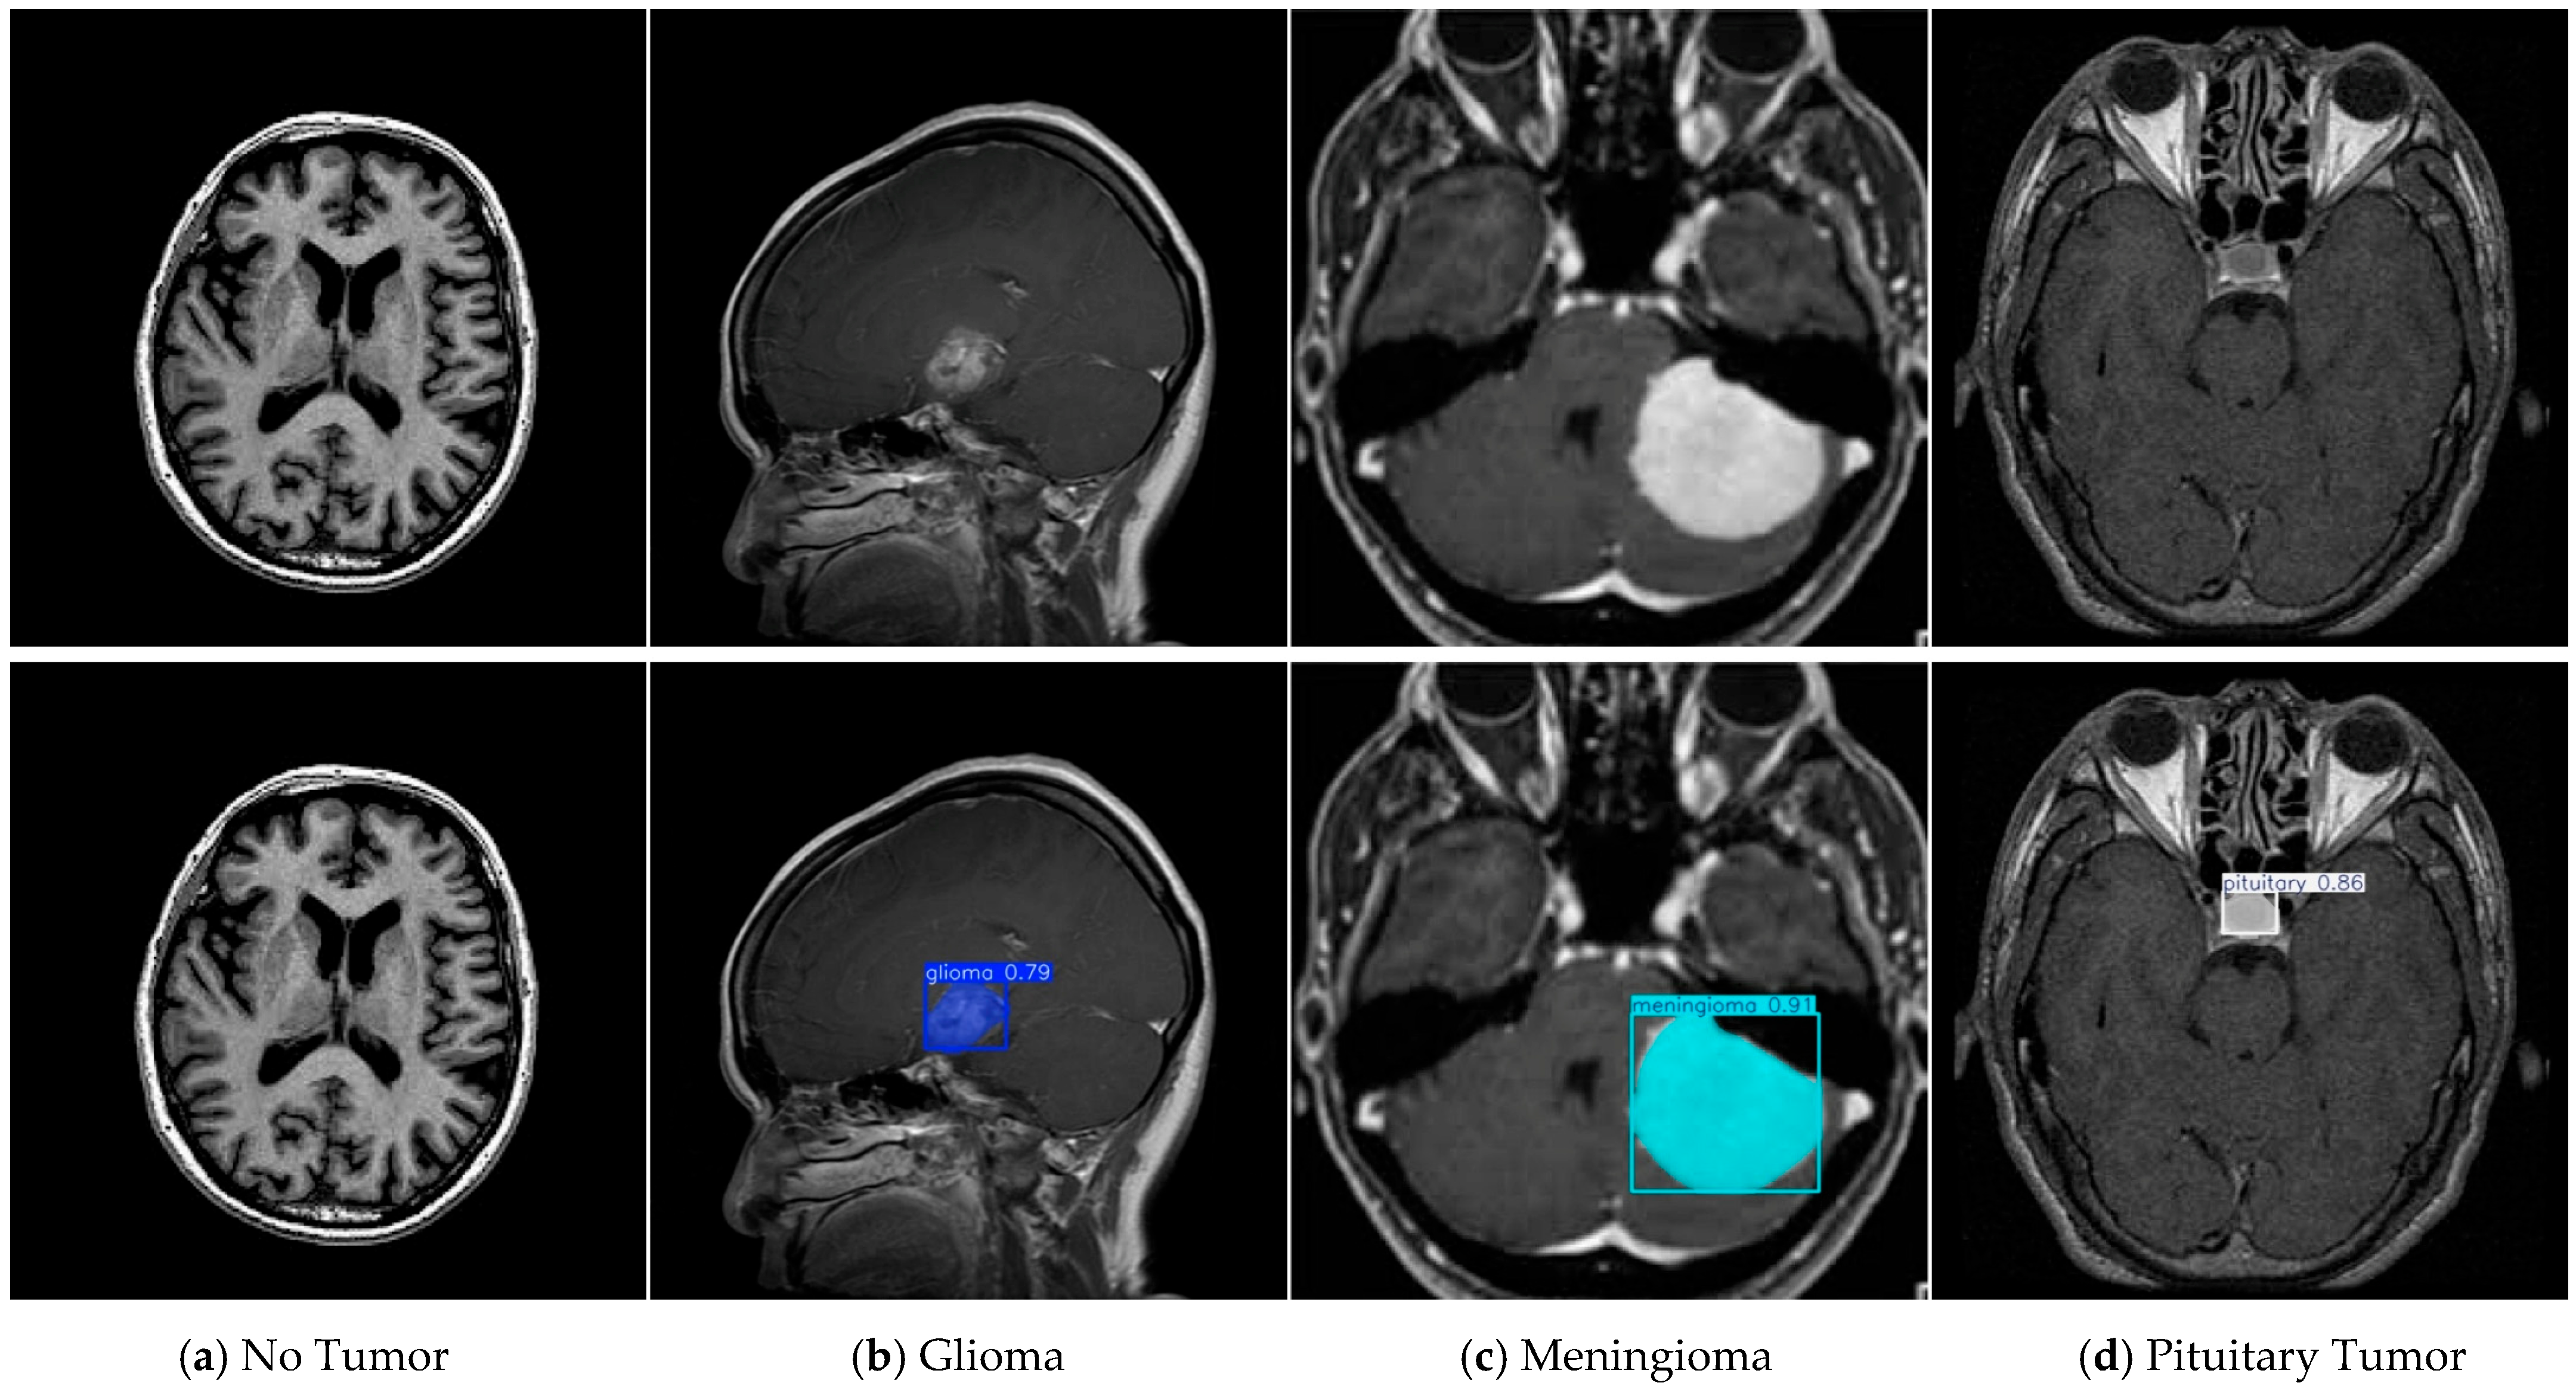

4.1. Dataset

- Roboflow. Tumor Otak > YOLOv8 Crop 15-85. Roboflow Universe. Available online: https://universe.roboflow.com/sriwijaya-university-hivwu/tumor-otak-tbpou (accessed on 13 August 2025).

- Roboflow. BRAIN TUMOR > Roboflow Universe. Available online: https://universe.roboflow.com/college-piawa/brain-tumor-j0l2c (accessed on 11 September 2025).

| Tumor-Otak | Total | Glioma | Meningioma | Pituitary Tumor |

|---|---|---|---|---|

| train | 2144 | 984 | 502 | 658 |

| val | 612 | 285 | 142 | 185 |

| test | 308 | 159 | 62 | 87 |